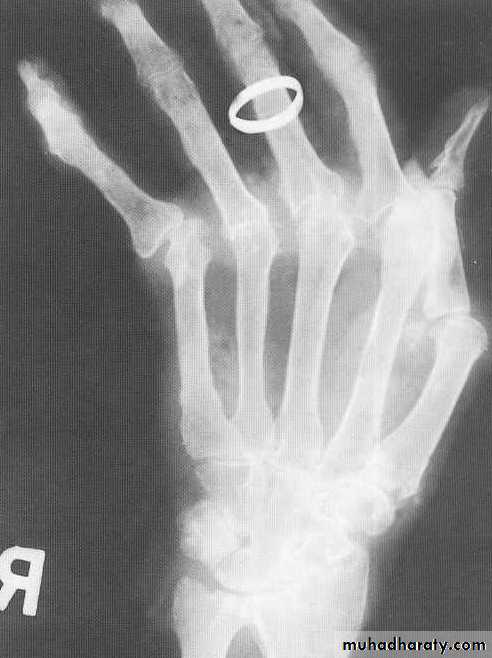

GOUT

• Heterogeneous group of entities characterized by recurrent attacks of arthritis secondary to deposition of sodium urate crystals in and around joints.• *90% of patients are male

• Radiographic features

• *Lower extremity > upper extremity; small joints > large joints

• * First MTP is most common site

• * Marginal, peri articular erosions: overhanging edge

• * Erosions may have sclerotic borders

• * Joint space is preserved

• * Soft tissue and bursa deposition

• Tophi: juxtaarticular, helix of ear

• Bursitis: olecranon, prepatellar

• * Erosions and tophi only seen in longstanding disease

• * Tophi calcification, 50%

• *Chondrocalcinosis